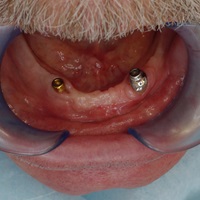

Pacjentka lat 72, od kilkudziesięciu lat chorująca na cukrzyce I typu, obecnie od 10 lat na pompie insulinowej. Profesor medycyny, siostrzenica pacjentki prowadzi swoją ciocię diabetologicznie, pacjentka świadoma zagrożeń przy zabiegach regeneracji kości i implantacji w takim ogólnym stanie zdrowia. Po rekonstrukcji tkanek miękkich i kości osadzono dwa implanty o średnicy 5,0 mm. Na zdjęciu śródzabiegowym widać zadowalające wyniki rekonstrukcji tkanki kostnej. Po upływie kilku miesięcy wykonano nadbudowę protetyczną.